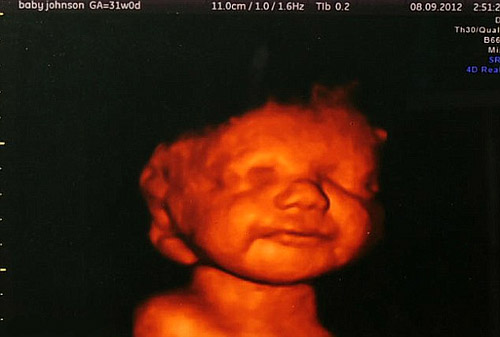

“We had our first scan when I was 3 months pregnant. Everything was really wonderful. As soon as we saw our baby we fell in love with him. Our future looked so promising…” Katyia says.

Katyia and Shane began to get ready for the important event. They decorated the baby's room. Katia studied all the information concerning her child's disease and was ready to anticipate any of his needs. "He was growing, kicking inside of me and despite he was not born yet, he already had his preferences", she recalls. For instance, he enjoyed... the shower. Each time Katyia directed water onto her tummy, the baby began to move - she felt that her son liked it. She also felt the other people's reaction to her attitude. Many people thought it was weird to behave like she did. "Every time I doubted if I were right or not, I took my son's "portrait" (that very 3D scan) where he smiled, and I understood I was right".